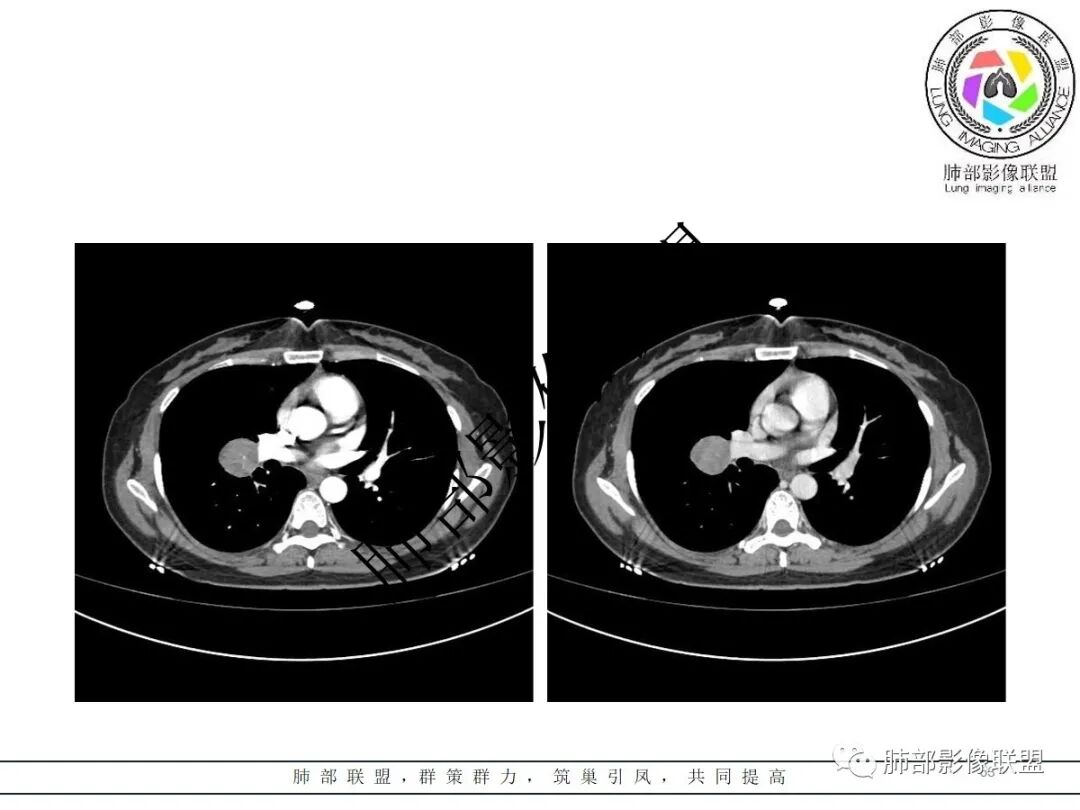

3.病灶密度均匀,未见液化坏死、钙化及脂肪低密度。轻度强化,可见纤细血管影蜿蜒穿行。右肺动脉推移变形,未见侵入或充盈缺损。

1)巨淋巴结增生症(CD)大多动脉期高强化,毕竟透明血管型占多数,本例特征不足。

3)硬化性肺细胞瘤(PSP)可以血管贴边,常常强化比较显著。

4)发生于肺表面(近脏层胸膜或叶间裂),强化不显著,可见穿行血管,与本例的符合程度是最高的。

3)CT増强多呈中度至明显均匀强化,多期扫描呈持续性强化,部分病灶早期强化不均匀,呈花斑状,延迟后强化较早期均匀;

4)瘤周可出现晕征、空气新月征及贴边血管征,若同时出现,诊断PSP的信心更好。